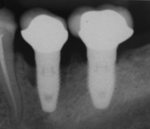

صورة شعاعية لغرسة السن.